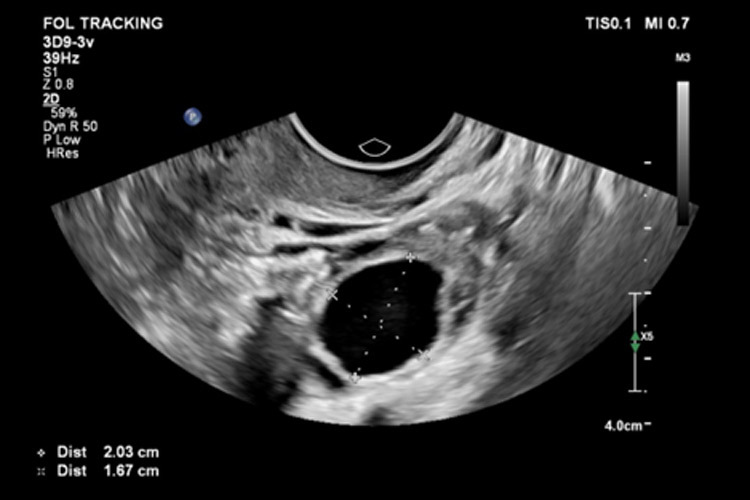

Η εικόνα παρουσιάζει μέτρηση ώριμου ωοθυλακίου με μέσο διάμετρο 18.5 mm της αριστερής ωοθήκης

Εξατομικευμένη καθοδήγηση: Η νέα μας προσέγγιση περιλαμβάνει στενή παρακολούθηση του αναπαραγωγικού σας κύκλου μέσω προηγμένης παρακολούθησης ωοθυλακίων. Κάθε βήμα είναι εξατομικευμένο στον μοναδικό βιολογικό σας ρυθμό, εξασφαλίζοντας ακρίβεια στον εντοπισμό του βέλτιστου χρόνου για σύλληψη. Γίνονται πολλαπλές εξετάσεις ενδοκολπικά ανώδυνα και υπολογίζεται το μέγεθος του κυρίαρχου ωοθυλάκιου αλλά και διαβεβαιώνεται πότε γίνεται η ωορρηξία. Το ζευγάρι προσαρμόζει τη συχνότητα επαφής με βέλτιστο τρόπο.

Τεχνολογία υπερήχων αιχμής: Αγκαλιάστε την άνεση της τεχνολογίας με την φιλική προς το χρήστη εφαρμογή μας. Λάβετε ενημερώσεις σε πραγματικό χρόνο για το παράθυρο γονιμότητάς σας, επιτρέποντάς σας να σχεδιάζετε τις προσωπικές σας στιγμές με σιγουριά. Το κέντρο διαθέτει υπερσύγχρονη υπερηχογραφική μηχανή επιτρέποντας τη διεξαγωγή του ανώτατου επιπέδου 3 γυναικολογικής υπερηχογραφικής εξέτασης